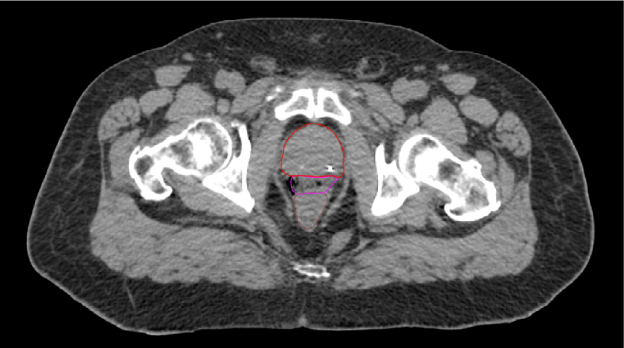

SpaceOAR-CT image.

A. SpaceOAR-CT

SpaceOAR-T2 MRI image.

B. SpaceOAR-T2 MRI

SpaceOAR Vue-CT image.

C. SpaceOAR Vue-CT

SpaceOAR Vue-T2 MRI image.

D. SpaceOAR Vue-T2 MRI

Figure 1. SpaceOAR Hydrogel vs. SpaceOAR Vue Hydrogel on CT and 1.5T T2 MRI simulation scans. Representative axial CT and T2 MRI simulation scan images from two patients who received perirectal hydrogel spacer with SpaceOAR Hydrogel (A, B) or SpaceOAR Vue Hydrogel (C, D). For SpaceOAR Hydrogel (A, B) hydrogel was contoured on MRI and modified based on CT, whereas for SpaceOAR Vue Hydrogel (C, D) hydrogel was contoured directly on the CT simulation scan. Note that for SpaceOAR Hydrogel (A, B) the T2 MRI hyperintense region in B between the prostate and rectal contours is not easily seen on CT in A. For SpaceOAR Vue Hydrogel, the hyperintense region on the T2 MRI in D corresponds to the hyperdense region between the prostate and rectum on CT in C. Red- prostate contour, Magenta- hydrogel contour, Brown- rectal contour.